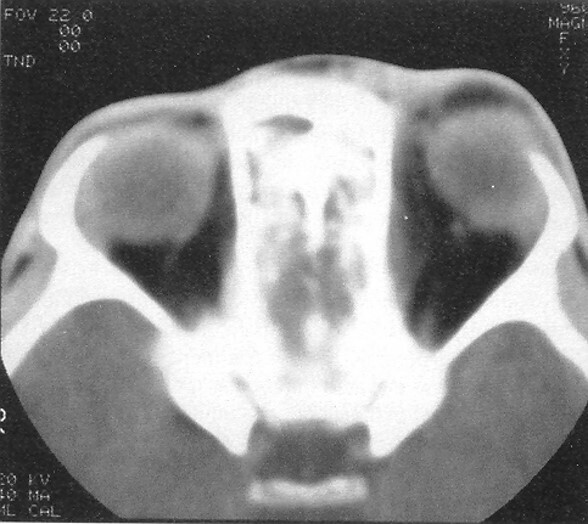

orbital cellulitis

A

-soft tissues posterior to orbital septum -> orbital fat, extraocular muscles, neurovascular tissues

-medical emergency

-MCC- bacterial sinusitis through ethmoid

-infants -> dacryocystitis

-systemic signs of infections

-swelling, fever, tender EOM, elevated IOP, impaired vision

-proptosis, chemosis, decrease visual acuity, ophthalmoplegia, optic neuropathy

-relative afferent pupillary defect (RAPD) aka marcus gunn ->

-clinical dx -> confirmed on CT orbits and sinuses

-blood cultures

-tx-

-empiric IV antibx -> vanco + ??

-surgery and urgent opth consult

-complications- visual loss (optic nerve), orbital compartment syndrome, systemic or CNS infection (meningitis), cavernous sinus thrombosis (bilateral), subperiosteal abscess